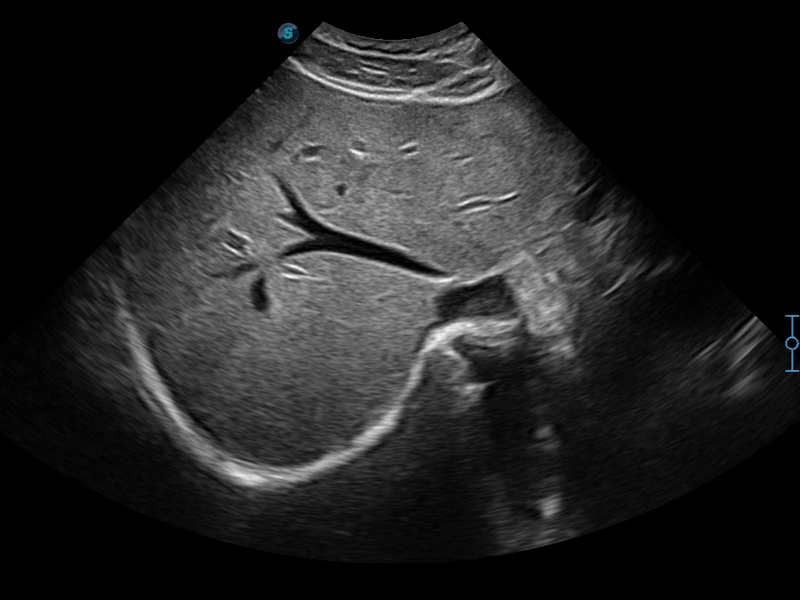

腔内探头

凭借狗万官方网站先进的成像技术和优异的探头技术提供的清晰的图像表现,您可以更自信地做出临床决策。